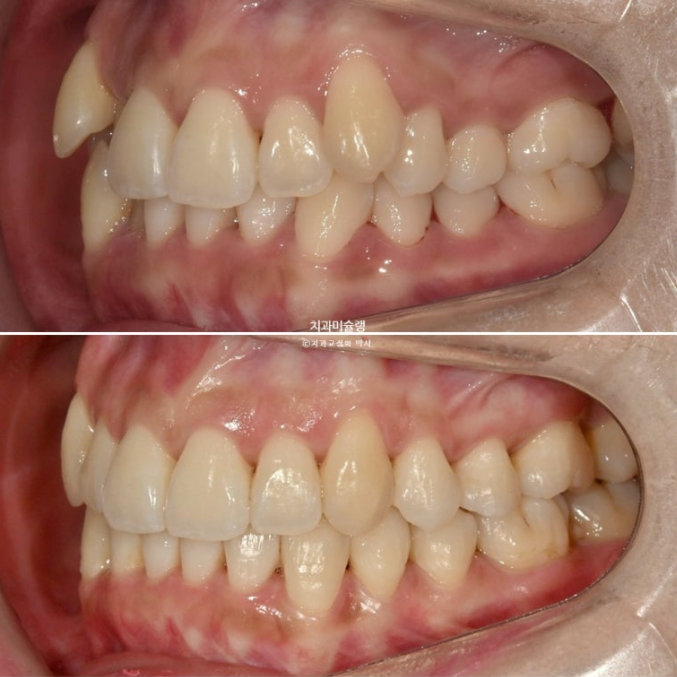

25.10

어금니 교합개선을 위해 재제작을 2번이나 한만큼 어금니 교합은 물샐틈 없는 1급 교합관계를 보입니다.

23.08~25.10

중심선의 개선, 과개교합의 개선, 덧니의 개선, 블랙트라이앵글의 개선이 보입니다.

앞니는 뒤로 들어가지도, 나오지도 않고 잘 유지되었습니다.